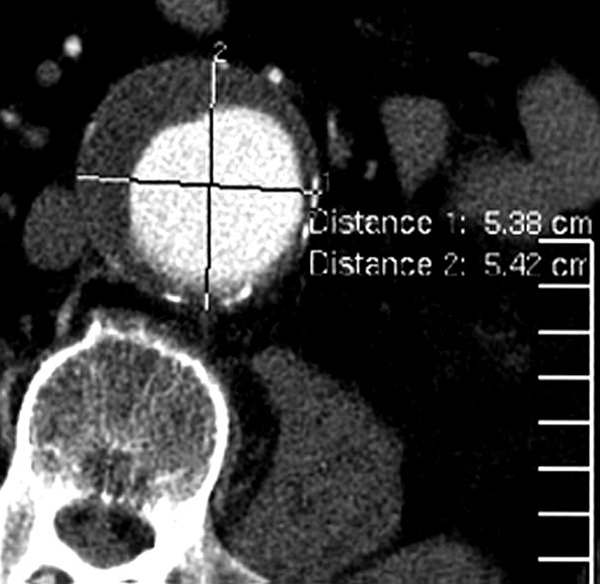

CT billede af maven med aortaaneurisme

Tværsnit (axial) CT billede efter, at der er givet røntgenkontrastvæske intravenøst (ind i en overfladisk vene på armen). Diffust (fusiformt) aneurisme (udposning) af legemspulsåren i maven (abdominale aorta). Den lyse del i centrum er der, hvor blodt strømmer (blodfyldt lumen). Ud mod aortavæggen ses mørkere halvmåneformet skygge. Dette er størknet blod inde i aneurismet (vægtrombe). Aneurismets største diameter er 5,4 cm, og måles fra aortas yderkant til yderkant.